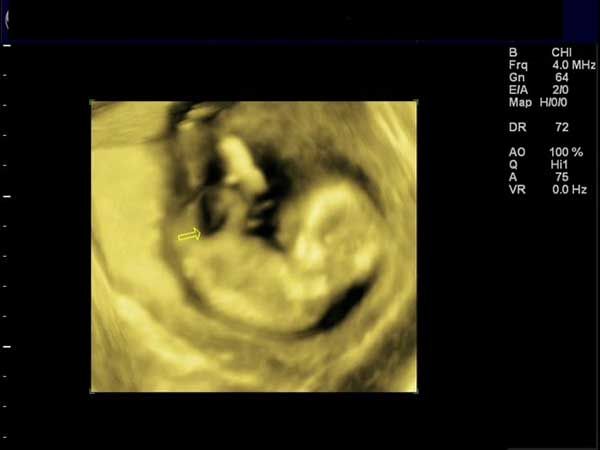

What is your diagnosis of this incidental finding during routine ultrasonography in a 15-week fetus?

Get the latest clinical updates, case studies, and expert commentary in obstetric and gynecologic care. Sign up now to stay informed.